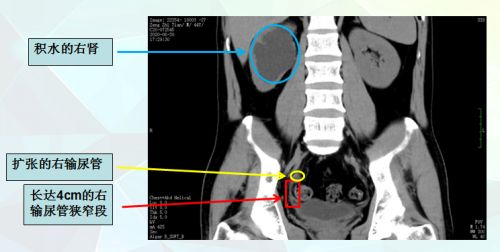

术前ct可以看到右输尿管狭窄段、扩张段以及肾脏积水。

郭玺副主任医师详细查看患者病史及各项检查资料发现,胡先生右侧输尿管下段入膀胱处有一段长达4cm内径仅1mm的狭窄,右肾还有明显的积水和扩张。“针孔大的输尿管通道必然会导致排尿不畅,如果不能有效并持久地扩开输尿管,久而久之必然引发肾积水、持续腰部钝痛和反复的泌尿系感染”,郭玺坦言,对于这种复杂的长段输尿管狭窄,无论是开放还是腹腔镜手术,疗效均不确切,且很难达到满意的效果。